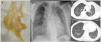

A 48-year-old woman with Noonan syndrome presented with episodes of repeated fever and dyspnea and occasional expectoration of large volumes of dense sputum followed by chest tightness and palpitations. Bronchial molds were observed when the sputum was evaluated (Fig. 1a). An X-ray and a computed tomography scan were performed showing ground glass parenchymal opacities (Fig. 1b and c) and a pattern of interlobular septal thickening (Fig. 1d). Pathology study of bronchial molds showed amorphic fibrinomucoid or arboriform material with nonspecific inflammation. With a diagnosis of plastic bronchitis and multilobar pneumonia, treatment began with levofloxacin and respiratory physiotherapy with resolution of the symptoms.

(a) Bronchial mold expected by the patient. (b) Posterior-anterior chest X-ray showing multilobar infiltrates in both lung fields. (c) Thoracic computed tomography showing multiple parenchymal opacities in tarnished glass with geographic distribution in both lung fields. (d) Chest computed tomography with smooth thickening of the interlobular septa in both lower lobes that in a patient with Noonan syndrome suggest the presence of lymphatic dysplasia.